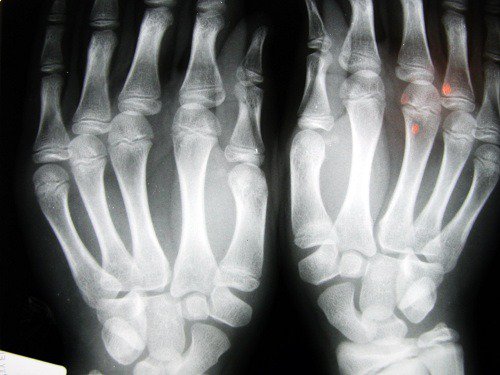

Ryzyko wystąpienia choroby zwyrodnieniowej stawów

Badanie przeprowadzone przez naukowców z Uniwersytetu w Nottingham (Wielka Brytania) wskazuje na to, że u osób, których palec wskazujący jest krótszy od reszty palców, ryzyko wystąpienia zapalenia stawów jest znacznie większe.

Problem ten – który w większości przypadków dotyczy kobiet – związany jest z niedoborem estrogenów i brakiem aktywności fizycznej.